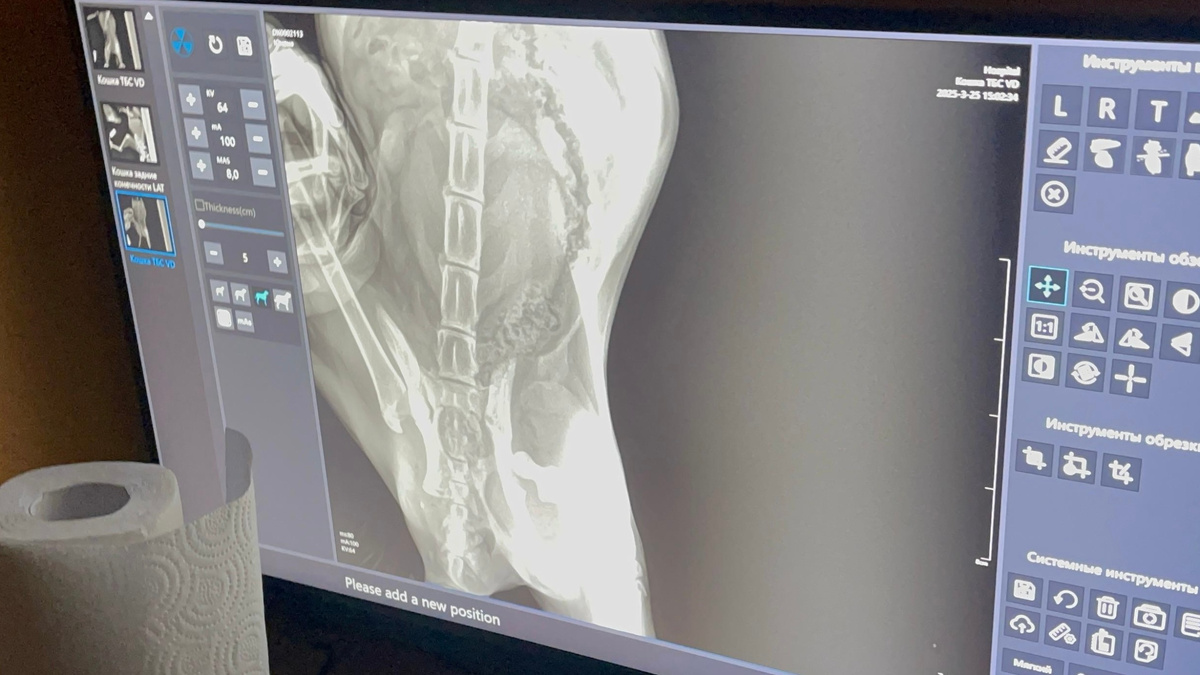

Очень ухоженная, красивая, нежная и ласковая кошечка. Сделали рентген... без комментариев...

Когда врач стал оперировать колено, он под наркозом сделал ещё один снимок и выяснилось, что у Юноны три пер'елома: бедро, колено и таз! Такое впечатление, что по ней проехалась машина! Вот до чего доводит самовыгул!